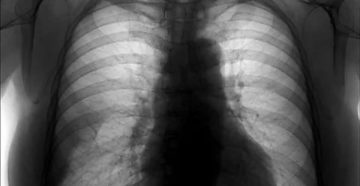

Киста легкого у взрослых: что это такое, симптомы, что делать и лечение При переводе с…

Пневмофиброз легких: что это такое, чем опасен и последствия, лечение народными средствами Пневмофиброз (пневмосклероз) –…